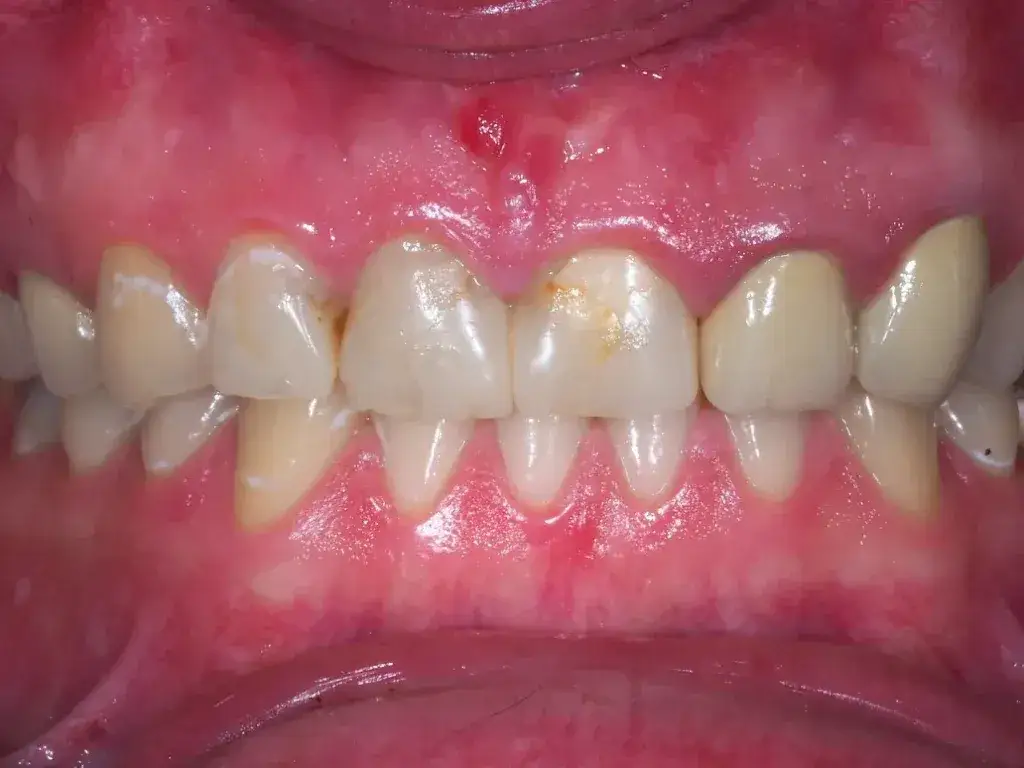

- Nagromadzenie płytki nazębnej i kamienia: To główna przyczyna zapalenia dziąseł (gingivitis), które objawia się zaczerwienieniem, obrzękiem i krwawieniem.

- Krwawienie dziąseł utrzymujące się ponad tydzień: Jeśli mimo stosowania domowych metod i poprawy higieny dziąsła nadal krwawią podczas szczotkowania lub jedzenia przez dłużej niż tydzień, to sygnał, że problem jest poważniejszy i wymaga profesjonalnej oceny.

- Silny, pulsujący ból dziąsła lub zęba: Ostry, nieustępujący ból, zwłaszcza pulsujący, może wskazywać na ropień, zaawansowane zapalenie dziąseł lub problem z zębem. Nie zwlekaj z wizytą, ponieważ infekcja może się rozprzestrzeniać.

- Widoczna opuchlizna lub ropień na dziąśle: Opuchlizna, często połączona z zaczerwienieniem i ciepłem, a zwłaszcza obecność ropnia (małej, bolesnej krostki wypełnionej ropą), jest objawem infekcji, która wymaga natychmiastowego leczenia.